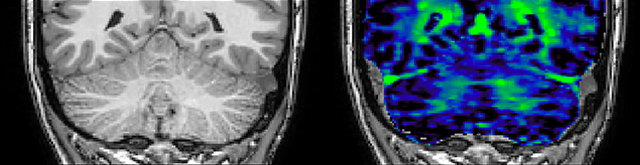

Myelin water imaging (MWI) is a breakthrough technique that was pioneered at UBC for measuring myelin content in the brain, in vivo. “Because the T2 time of water in myelin is much shorter than the T2 of water in the intraand extracellular spaces, we can separate out the myelin water signal.”

The techniques for measuring myelin have changed a lot over the years. “Since we are using the Elition, our myelin water images are much better. We're now acquiring 1 x 2 x 5 mm voxels and displaying at 1 x 1 x 2.5 mm. For a whole brain we can now measure the fraction of water in the myelin component in only about five or six minutes,” Dr. MacKay says.

of limiting MWI to the brain, even without the cerebellum, we can now spend about the same amount of time and scan the whole brain and the cervical spinal cord, which is a huge boost for us.” Dr. Rauscher says, “For MWI we perform 3D T2 with 32 or more echoes. This used to take a long time, but with Compressed SENSE we can decrease this to ten minutes for the whole head. Because of the large field of view (FOV) on the readout direction, we even get information from the brainstem, which we previously missed when we were using the GRASE approach. Having the whole head scan is nice because it has spatial resolution, orientation and FOV that are comparable to the standard 3D clinical MS scans, including the FLAIR and 3D T2, and a 3D T1 for brain volume.”

T1 - Weighted, Myelin Water Fraction Superimposed

Spinal cord coverage

Smaller, more isotropic voxels

Excellent detail in quantitative maps

Images courtesy of Adam Dvorak, Department of Physics and Astronomy, University of British Columbia